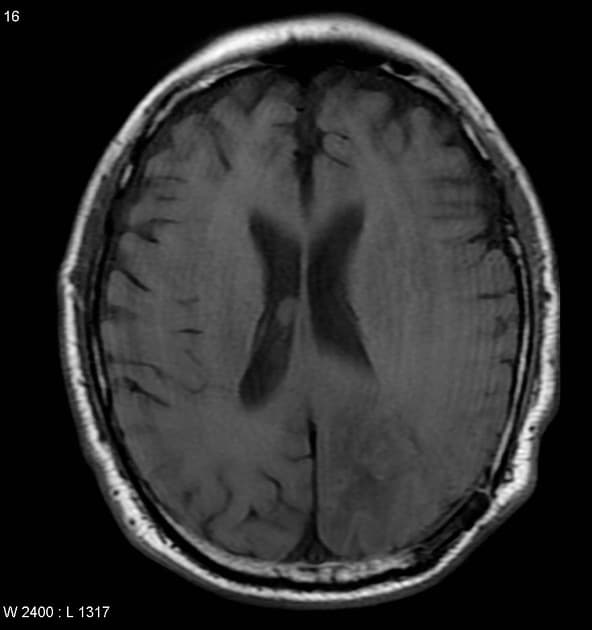

- Khối bắt thuốc dạng viền (ring-enhancing mass) ở thuỳ trán sau bên trái, kèm theo một lượng nhỏ phù vận mạch (vasogenic edema) xung quanh.

- Có một phần hạn chế khuếch tán (diffusion restriction) ở vùng ngoại vi, nhưng không có ở trung tâm.

Lesion "hoàn hảo" bắt thuốc dạng viền, nhưng không phải là áp xe não (do không có hạn chế khuếch tán ở trung tâm trên hình ảnh khuếch tán – DWI và lượng phù tương đối ít). MAGIC DR là từ viết tắt gợi nhớ hữu ích cho hình ảnh này.

- "Lượng phù xung quanh tổn thương ít tương đối so với kích thước gợi ý u thứ phát hơn là u thần kinh đệm độ cao."